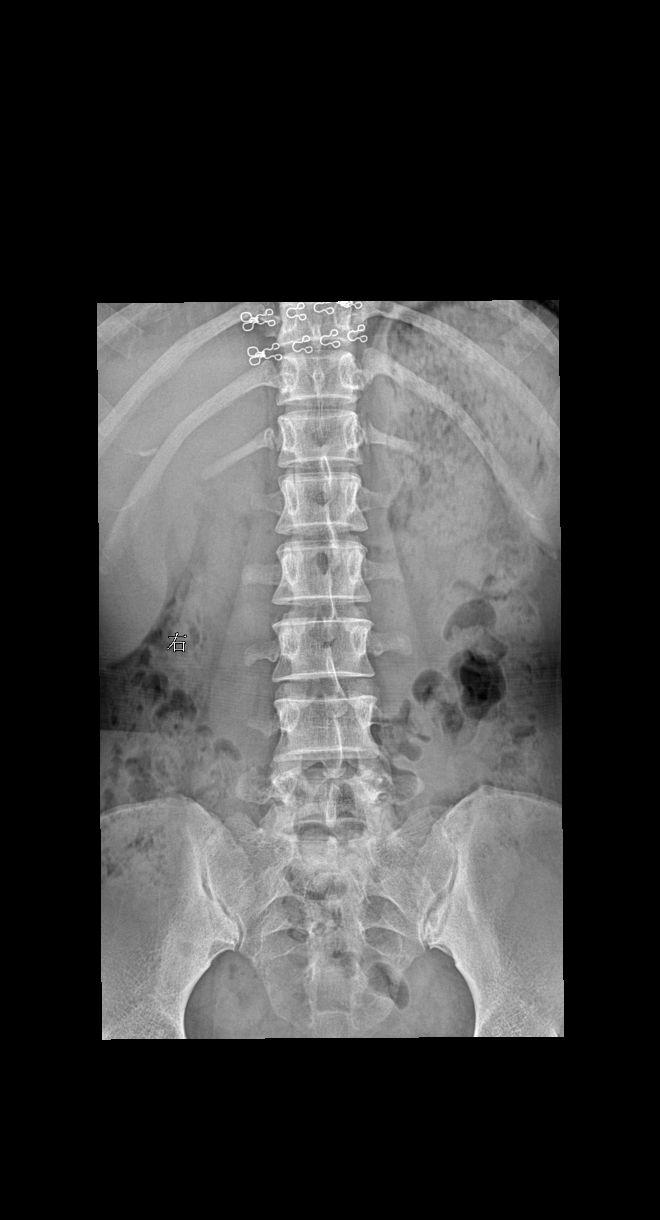

男 55 腰部疼痛就诊